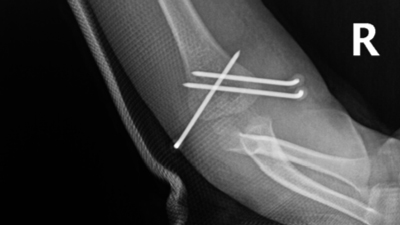

骨折部位术后

这是一种无切口、痛感小的微创治疗方法,手术过程通常不到1小时,经皮打入克氏针,骨折愈合即可取针。这种治疗方法不仅疗程相对较短,并且效果佳,不会留下大的伤疤,患处畸形发生率低。据了解,儿童骨骼与成人存在着巨大的差异,儿童处于持续生长发育的过程,除了关节骨折,大多数骨折复位到不影响正常活动即可,特别是四肢的骨折,尽量不切开复位,采取闭合复位,这样术后小朋友骨折恢复速度就会加快,且对生长发育的影响最小。